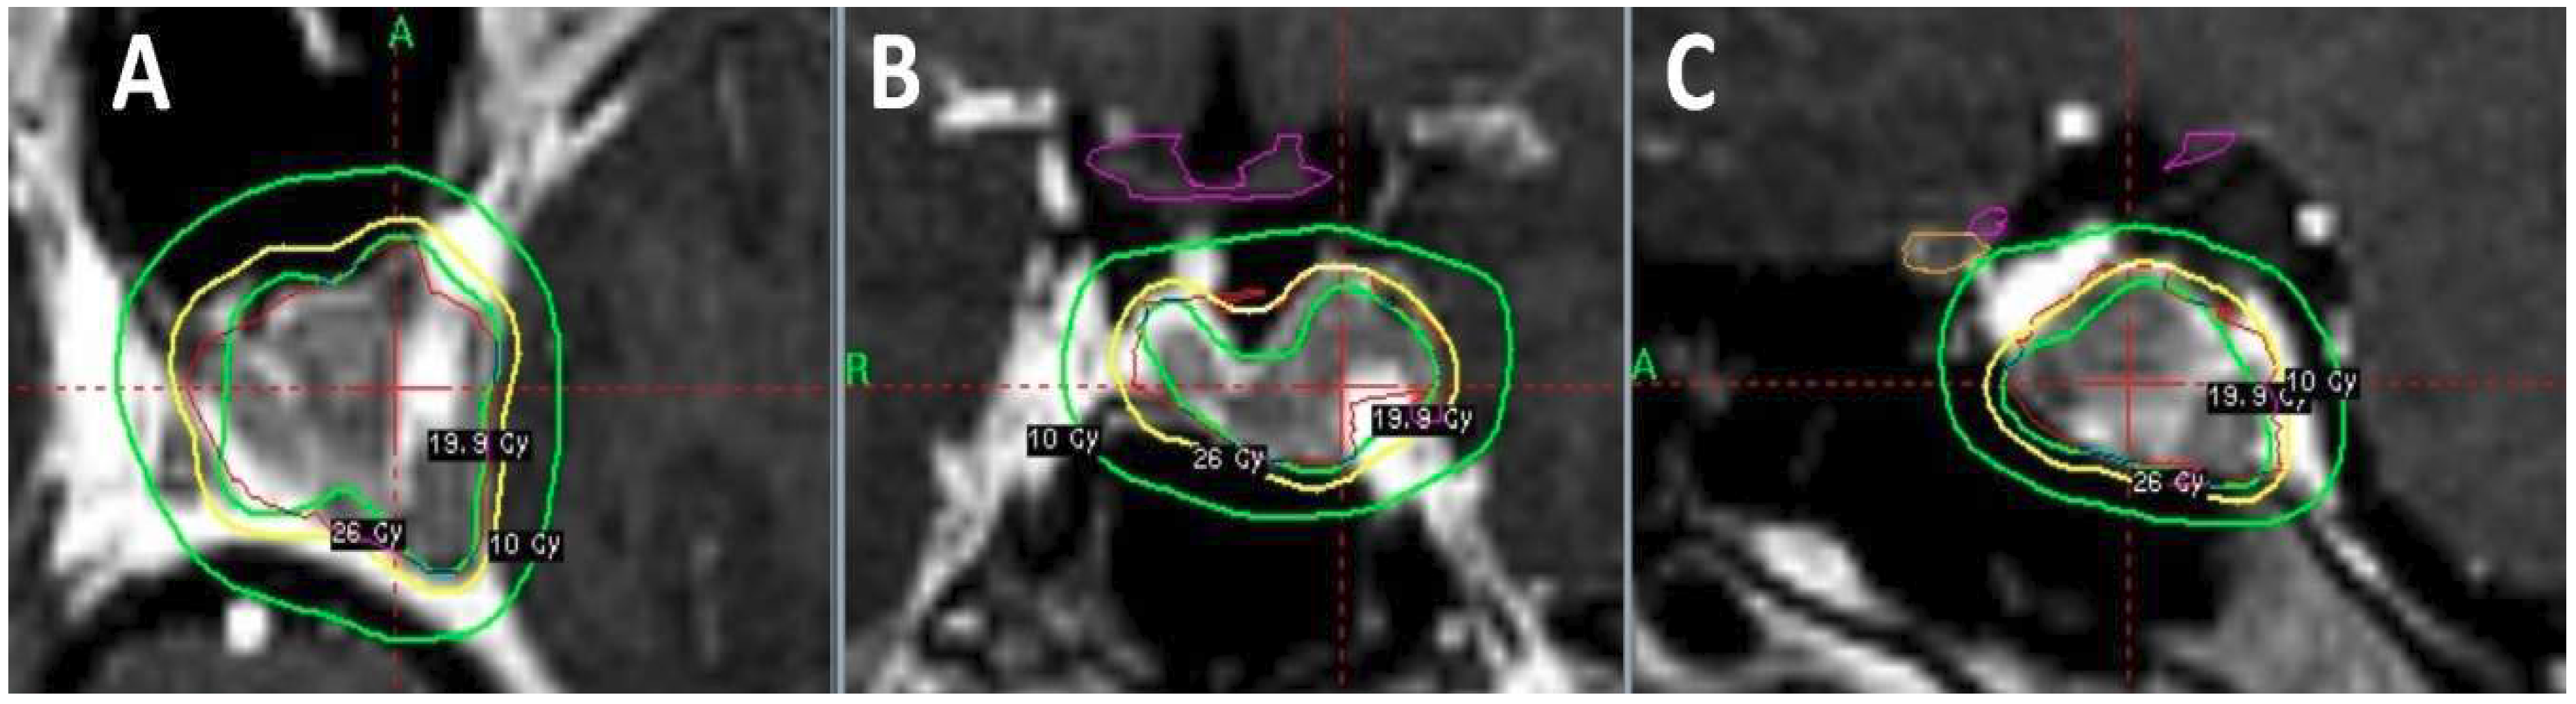

- Beltran, C.; Roca, M.; Merchant, T.E. On the benefits and risks of proton therapy in pediatric craniopharyngioma. Int. J. Radiat. Oncol. Biol. Phys. 2012, 82, e281–287. [Google Scholar] [CrossRef] [PubMed]